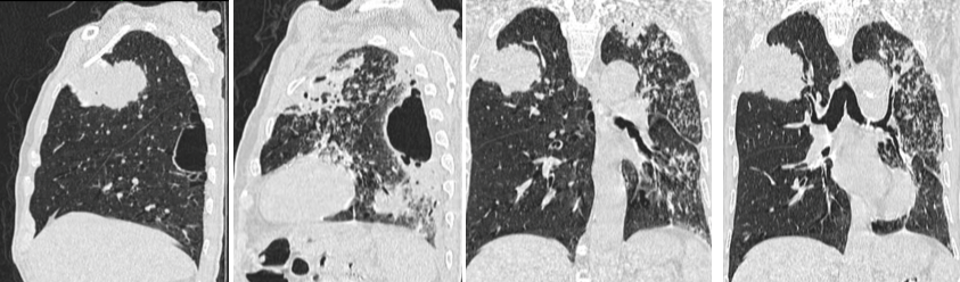

1 / 5

Homme, 80 ans, tabagique et hypertendu;

Installation progressive depuis 2 mois: dyspnée, toux, bronchorrhée et amaigrissement.